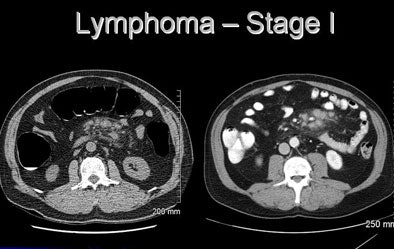

![]() |

| At VC, extracolonic CT images suggested abnormal mesenteric lymphadenopathy. Stage 1 lymphoma was confirmed at surgery. |